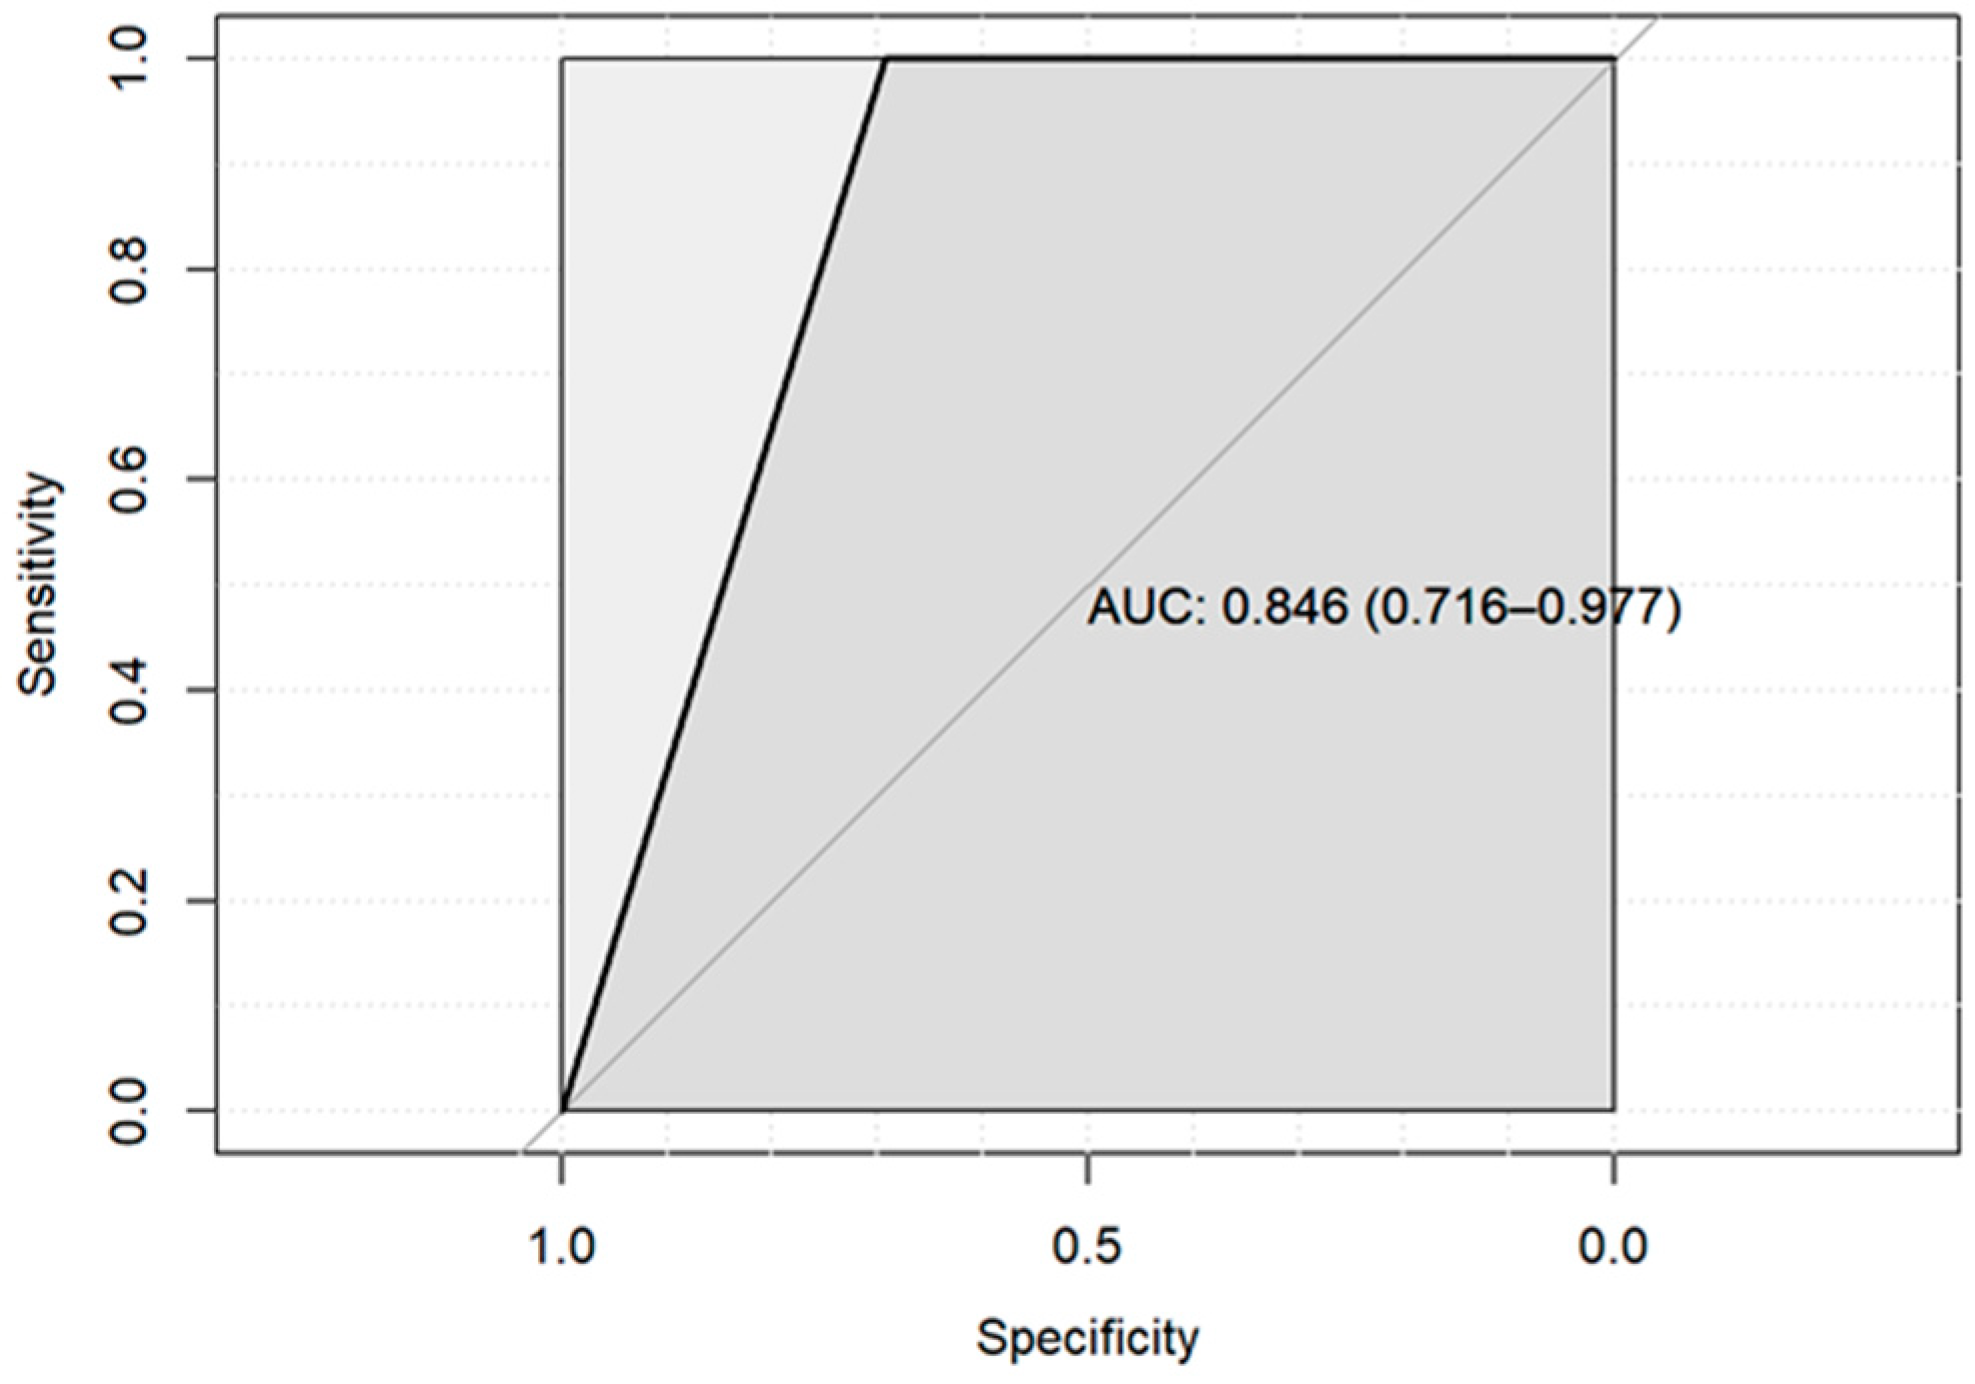

| Entropy | 0.048 * | −1.43 ± 0.69 | 0.033 * | −6.32 ± 2.97 | 0.285 | 0.067 | ||||

| Sphericity | 0.032 * | 1.84 ± 0.86 | 0.024 * | 2.57 ± 1.138 | 0.327 | 0.089 | ||||

| 3D diameter (cm) | 0.041 * | −1.47 ± 0.72 | 0.034 * | −2.29 ± 1.08 | 0.913 | 0.045 * | −1.75 ± 0.87 | 0.040 * | −1.88 ± 0.91 | |

| 2D diameter (Slice) (cm) | 0.038 * | −1.40 ± 0.68 | 0.028 * | −2.16 ± 0.98 | 0.961 | 0.056 | ||||

| Major axis length (cm) | 0.038* | −1.57 ± 0.76 | 0.035 * | −2.121 ± 1.01 | 0.949 | 0.044 * | −1.34 ± 0.67 | 0.042 * | −1.428 ± 0.71 | |

| Entropy | 0.046 * | −17.80 ± 9.93 | 0.024 * | −23.87 ± 9.53 | 0.240 | 0.085 | ||||||

| Skewness | 0.061 | 0.016 * | −20.88 ± 7.73 | 0.024 * | −21.63 ± 8.52 | 0.037 * | −17.37 ± 7.75 | 0.048 * | −18.05 ± 8.49 | |||

| 3D diameter (cm) | 0.017 * | −21.44 ± 8.07 | 0.009 * | −26.47 ± 8.89 | 0.477 | 0.051 | ||||||

| 2D diameter (Slice) (cm) | 0.038 * | −19.18 ± 8.52 | 0.026 * | −23.39 ± 9.50 | 0.609 | 0.087 | ||||||

| 2D diameter (Row) (cm) | 0.027 * | −20.59 ± 8.49 | 0.015 * | −26.37 ± 9.54 | 0.819 | 0.034 * | −18.94 ± 8.28 | 0.040 * | −19.43 ± 8.75 | |||

| Major axis length (cm) | 0.008 * | −23.55 ± 7.77 | 0.006 * | −26.85 ± 8.32 | 0.531 | 0.041 * | −18.84 ± 8.60 | 0.055 | ||||

| Least axis length (cm) | 0.007 * | −27.45 ± 9.00 | 0.004 * | −33.07 ± 9.8 | 0.528 | 0.113 | ||||||